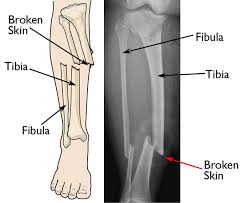

This is known as

What is a compound fracture?